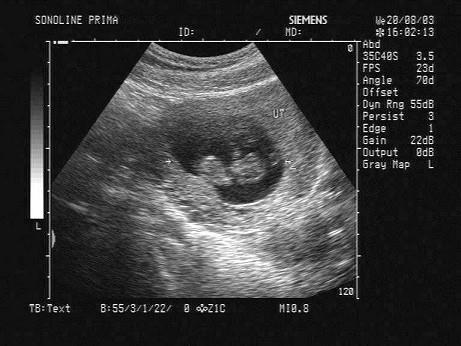

问题 下图为宫内孕囊声像图,可见心管搏动,该胎儿至少大于多少周?(?)

选项 A.6周 B.9周 C.10周 D.12周 E.8周

答案 A